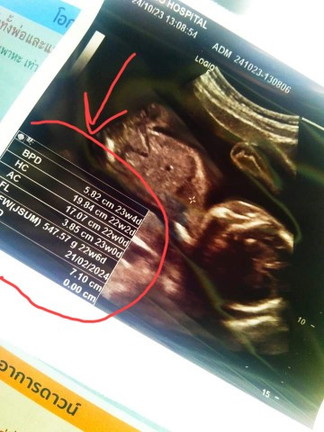

อยากทราบที่วงใว้ว่าคืออะไรค่ะเเม่ๆท้องเเรกค่ะ หมอไม่ได้บอกอะไรบอกเเค่ว่าน้องมีจู๋ค่ะ.🙏🥺

BPD = ขนาดศีรษะของน้อง HC = เส้นรอบศีรษะของน้อง AC =ขนาดท้องของน้อง FL =กระดูกต้นขาของน้อง ผลรวมทั้งหมด 4 อย่างนี้จะบ่งบอกน้ำหนักตัวน้อง

Đọc thêmขนาดต่างๆ ที่เครื่องวัดได้ มีน้ำหนัก อายุครรภ์และอื่นๆ